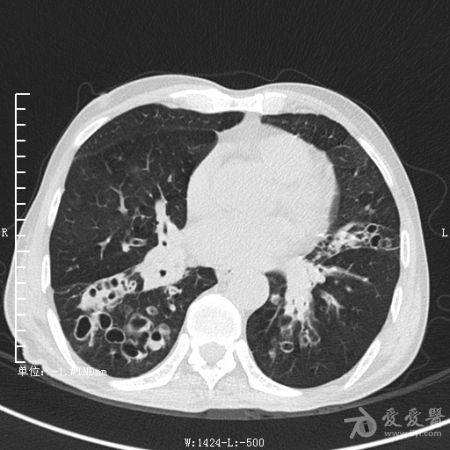

典型支气管扩张及肺水肿CT片

典型支气管扩张肺水肿